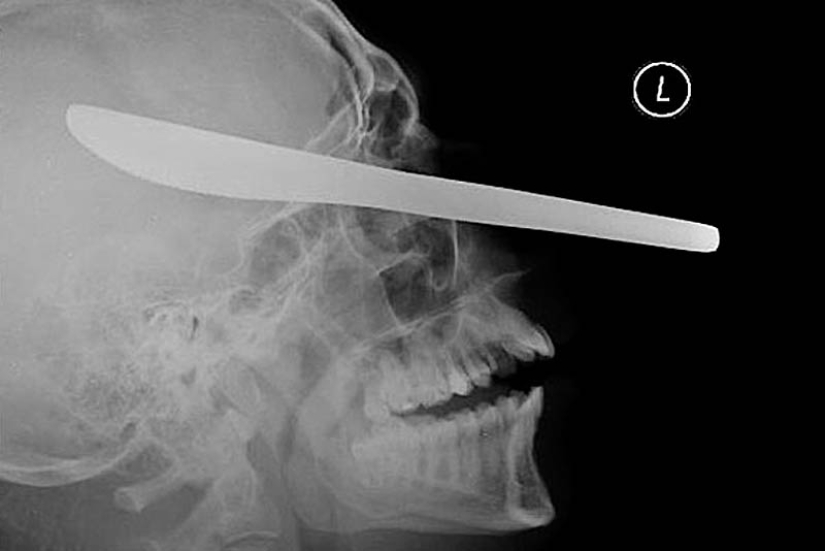

19. A knife for cutting oil in the patient's eye.